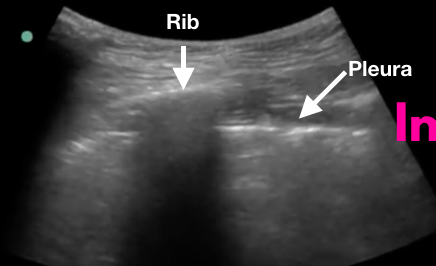

Poumons Antérieurs (S)

Glissement du poumon = pas de pneumothorax